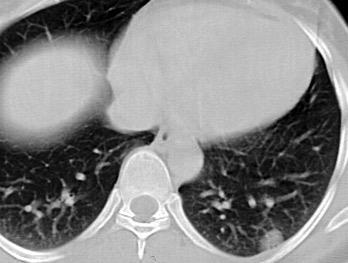

Densidad similar al músculo con estriaciones internas de grasa

Hallazgo incidental . Región infraescapular 2% de TC del tórax. Bilateral 60%.

Burt AM et al. Imaging review of lipomatous musculoskeletal lesions. SICOT J2017/ Murphey MD et al. From the archives of the AFIP: benign musculoskeletal lipomatous lesions. Radiographics. 2004